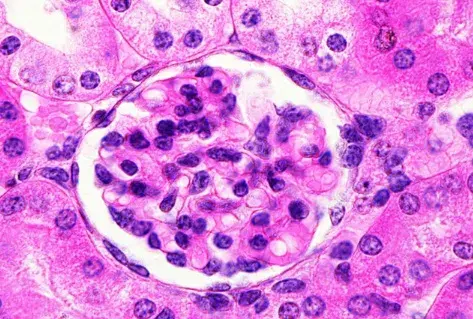

Nefropatía Membranosa: ¿Y si el paciente no responde al tratamiento inicial?

Nefropatía Membranosa: ¿Y si el paciente no responde al tratamiento inicial?

Cómo tratar la Nefropatía Membranosa de manera práctica

Cómo tratar la Nefropatía Membranosa de manera práctica